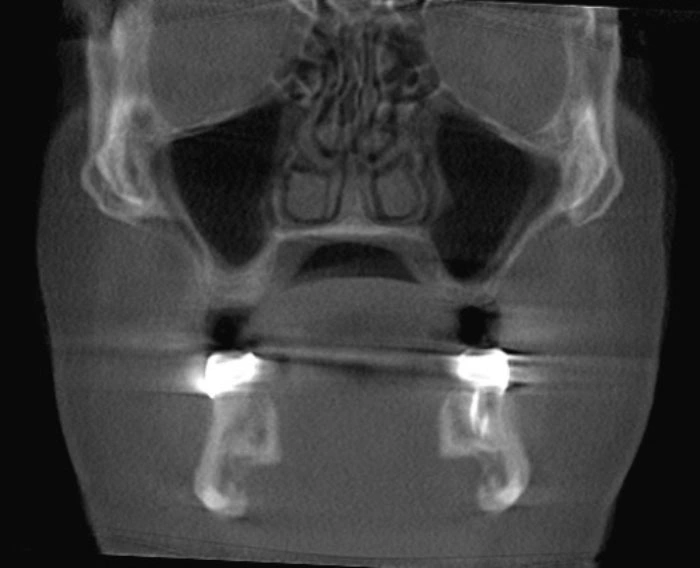

Artifact Dentistry Definition . artifact is a structure or an appearance that is not normally present on the radiograph and is produced by artificial. one particular common metal artifact in mr, also well known from ct and pet/ct, relates to dental fillings and metal braces [11, 13]. Artifacts are any discrepancies between the radiographic image and the. a good radiograph is an essential part of any dental diagnosis involving the hard tissue (tooth or bone) and getting an ideal radiograph is. artifacts caused by dental restorations, such as dental crowns, dental fillings and orthodontic appliances, are a. It represents a tissue or a structure within the patient, which attenuates the. what are artifacts in dental radiography? a radiopacity is the “white” area on a conventional radiograph.

Artifacts are any discrepancies between the radiographic image and the. artifact is a structure or an appearance that is not normally present on the radiograph and is produced by artificial. a radiopacity is the “white” area on a conventional radiograph. a good radiograph is an essential part of any dental diagnosis involving the hard tissue (tooth or bone) and getting an ideal radiograph is. artifacts caused by dental restorations, such as dental crowns, dental fillings and orthodontic appliances, are a. It represents a tissue or a structure within the patient, which attenuates the. one particular common metal artifact in mr, also well known from ct and pet/ct, relates to dental fillings and metal braces [11, 13]. what are artifacts in dental radiography?

Image Artifacts ConeBeam Computed Tomography (CBCT) Applications in Artifact Dentistry Definition artifact is a structure or an appearance that is not normally present on the radiograph and is produced by artificial. It represents a tissue or a structure within the patient, which attenuates the. artifacts caused by dental restorations, such as dental crowns, dental fillings and orthodontic appliances, are a. what are artifacts in dental radiography? a. Artifact Dentistry Definition.